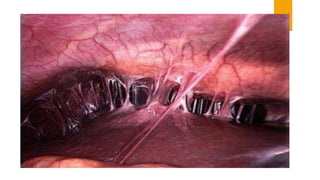

 LAPAROSCOPY- It is considered as the GOLD STANDARD and is the most reliable

• MILD:- Tubes: edema, erythema, no purulent exudates and are mobile.

• MODERATE:- Purulent exudates from the fimbrial ends, tubes not freely movable.

• SEVERE:- Pyosalpix, inflammatory complex, abcess

• ‘VIOLIN STRING’:like adhesions in the pelvis and around the liver suggests chlamydial

infection.

 LAPAROSCOPY- Itis considered as the GOLD STANDARD and is the most reliable aid to support the clinical diagnosis. The laparoscopic findings and the severity of PID • MILD:- Tubes: edema, erythema, no purulent exudates and are mobile. • MODERATE:- Purulent exudates from the fimbrial ends, tubes not freely movable. • SEVERE:- Pyosalpix, inflammatory complex, abcess • ‘VIOLIN STRING’:like adhesions in the pelvis and around the liver suggests chlamydial infection.  Investigations are also to be extended to male partner and smear and culture are made urethral secretion.